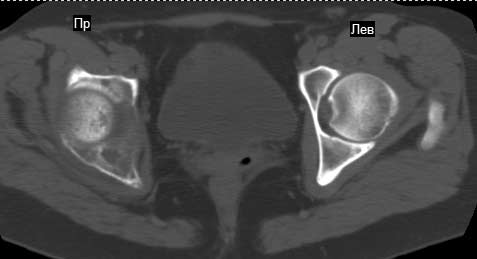

Сохранная по соматической патологии женщина ,47 лет. В 1996 г. установлен диагноз- cr левой молочной железы Т2N1Mo (2б)- проведено комплексное лечение- мастэктомия по Холстеду, ДГТ, 5 курсов ПХТ по схеме CMF. Сейчас менопауза уже 6-7 лет. В декабре 2004 года на профилактической остеосцинтиграфии с Тс99- выявлен единичный очаг повышенной фиксации препарата в зоне правой седалищной кости, рекомендована Рентгенография костей таза, выполнена- без патологии. УЗИ брюшной полости и Р-графия легких от конца апреля 2005 года - без патологии. Приблизительно 3 месяца назад появился болевой синдром в правом т/бедренном суставе с тенденцией к усилению. На рентгенограмме таза от мая 2005 года по заключению Рентгенолога очагов остеодеструкции не выявлено. Сегодня сделал ей Кт костей таза (картинки в приложении)- очаг деструкции в правой седалищной кости в зоне крыши вертлужной впадины.Что можно и нужно сделать? Жду советов, мнений, предложений по дальнейшей тактике ведения больной. С уважением, Корнев А.В.

Сам не имея опыта лечения подобных больных, сегодня показал представленные снимки специалисту по костной онкологии (Dr. Kurt Merkel), партнеру по работе.

Его мнение: в данный момент облучение не более 2000-3000 рад, через три недели операция по удалению процесса "кюретажным методом" затем ввести несколько спиц с резбой на конце в различных направлениях (создавая как бы внутренную арматуру) метод Harrington?, потом полость залить цементом, вариант костной пластики тоже не исключает.